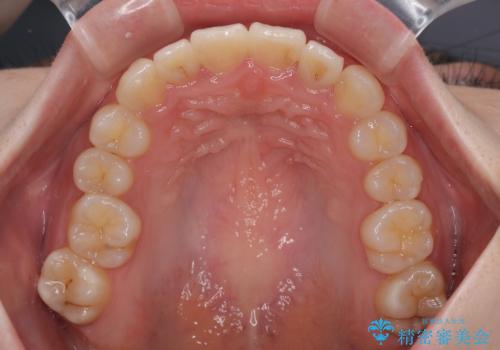

飛び出した前歯を引っ込める ワイヤー装置の非抜歯矯正

右上と左下の第一大臼歯2本が周辺の歯と比べて位置がずれていたため、ゴムかけやワイヤーに曲げを入れることで移動を試みましたが、どうよら癒着をしており、移動困難と判断されました。

見た目や咬み合わせに違和感がないとのことで、癒着歯の無理な移動は試みずに治療を終えることとしました。